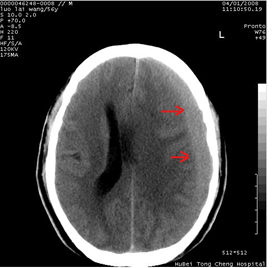

图1:红箭头:慢性硬膜下血肿

在老百姓眼中,颅脑疾病尤其是出血常常起病突然,发病较急,而慢性硬膜下血肿则明显不同,其在老年群体中多发,患者往往仅在病发几月前有轻微头部外伤史,甚至没有明显外伤。其主要表现为轻微的头痛,症状会随着血肿增大逐渐加重,逐步出现记忆力下降,四肢乏力等表现,而当血肿逐步增大至临界点时,症状常突然变化加重,严重的患者大脑中线偏移明显,甚至诱发脑疝,危及生命!因此,广大患者更应引起警惕,若有不适,需及时就诊!